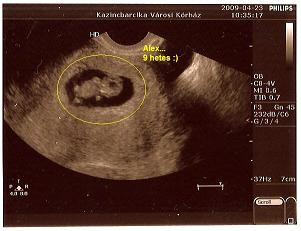

2009.04.24 06:35